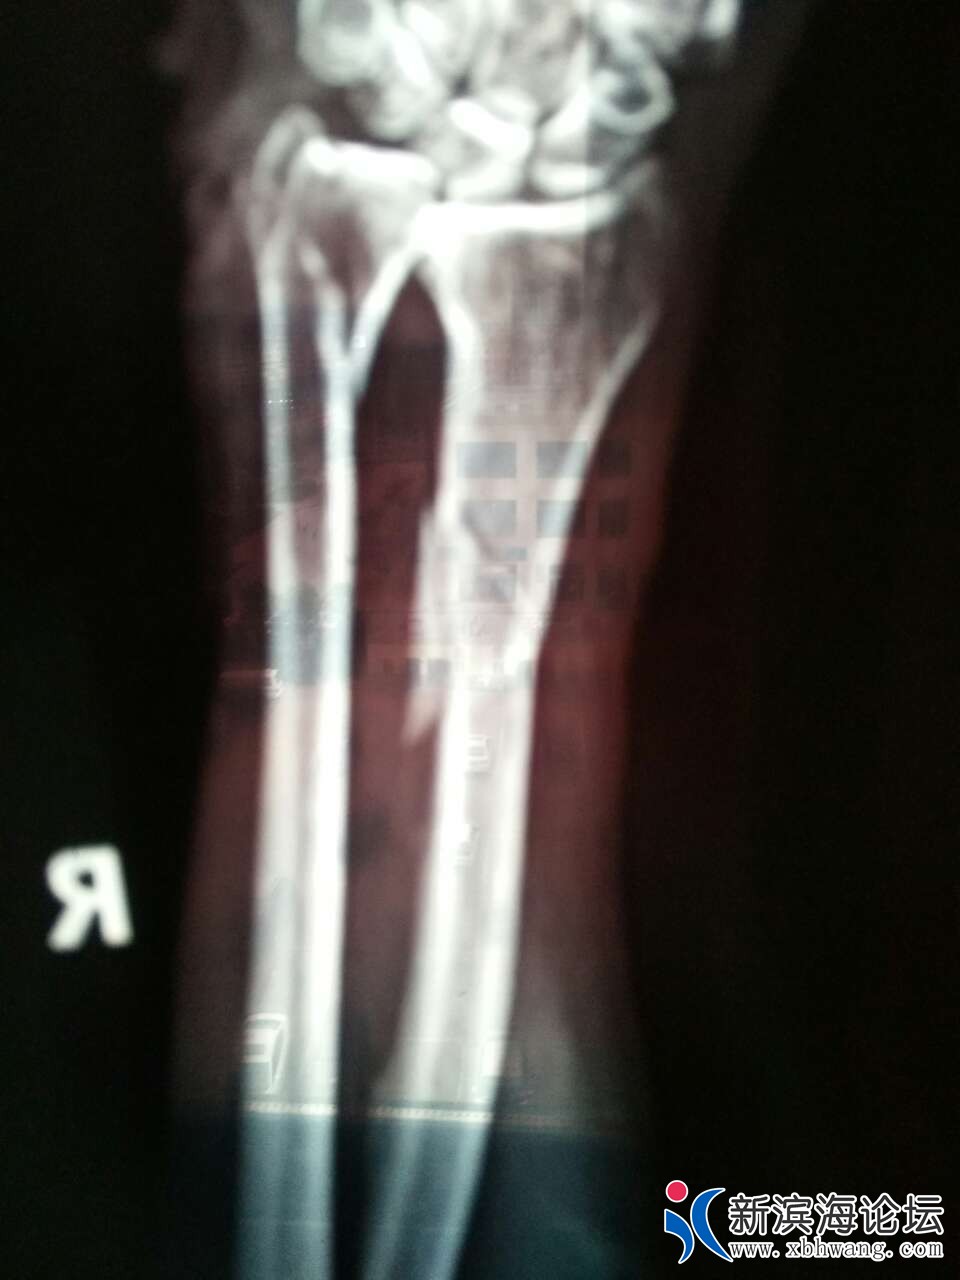

2019年06月28号供电局通知:《因新的变电所投运搭接施工,定于本月29(即星期六明天)全乡停电一天(早7点至晚7点,请看到的朋友相互轻告,提前做好停电准备工作。(注雨天顺廷)》这是原通知。由于搭线把380伏电接反了、导致动力电电机反转(天场乡、大套乡、所有380动力全部反转)造成人员伤害、导致手臂骨折,骨折四处手掌手臂多处撕裂伤。供电公司有没有责任?